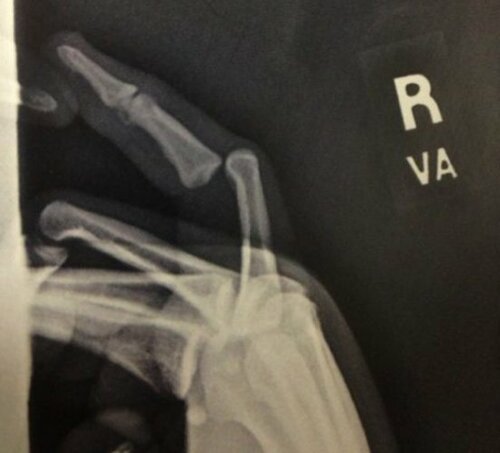

• Anthony Davis of the Hornets tweeted a picture of his very broken finger.

• Georgia State running back suffers a broken finger

• NFL wide receiver Torry Holt has a horribly disfigured finger